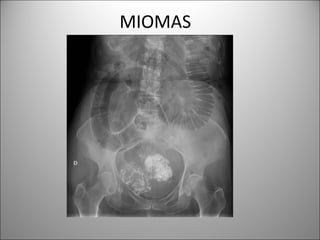

MIOMAS